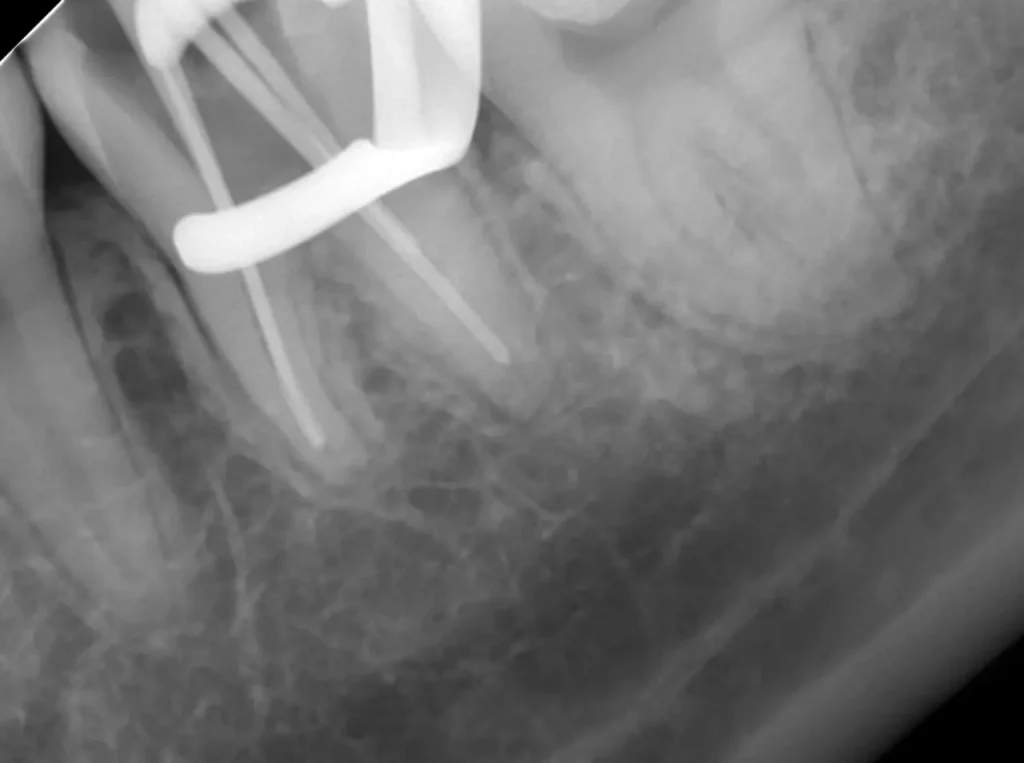

術中(ファイル試適)

レントゲン写真

ラバーダムシートを固定する金具が写っています、シートはバイ菌が

入らないように撮影時にも外しません